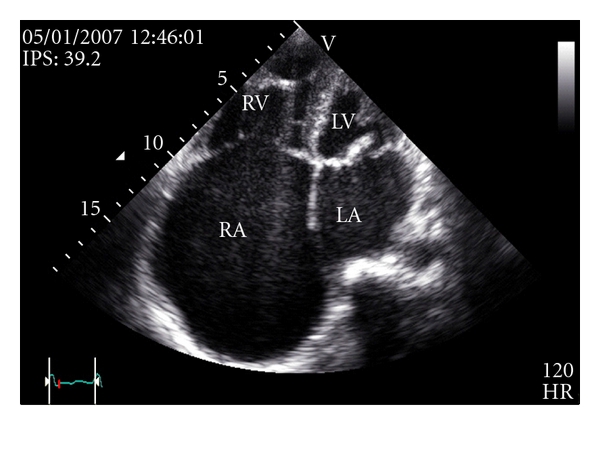

A chest radiography (Figure 1) revealed a marked cardiomegaly suggesting massively dilated right atrium (RA).